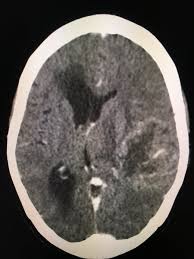

Computed tomography ct scan revealed symmetrical ventricular dilatation. Ported as a very common cause of shunt dysfunction 5 5. After placement of vp shunt the air introduced to the brain and the patient developed tension pneumocephalus which is neurosurgical emergency.

3 the purpose of ventriculoperitoneal shunt vps surgery is to allow csf flow through a shunting mechanism from the intracranial ventricles to the peritoneum. Ct brain revealed pneumoventricle and extensive subdural pneumocephalus overlying bilateral frontal lobes causing compression of the frontal lobes and separation of their tips characteristic of the mount fuji sign fig. In 126 frontal approach 48 malfunction and obstruction with shunt revi sion were seen.